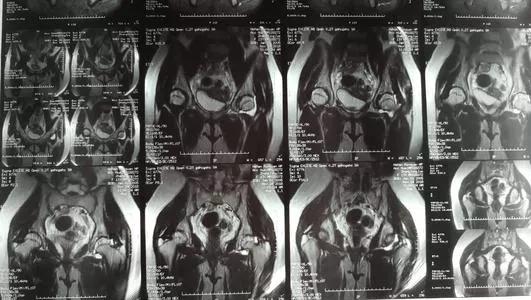

在膝关节存在症状的患者,应检查膝关节,除外其他疾病。这个疾病根据患儿的体征和症状基本可以诊断清楚,检查呢,可以做个磁共振看一看!一般表现是髋关节内可见有积液!B超检查也可以诊断!查血白细胞总数正常,或轻微升高。血沉正常或轻微升高,若血沉升高明显,超过20mm/h,结合体温升高超过37.5℃,白细胞计数增高等,提示感染性关节炎。